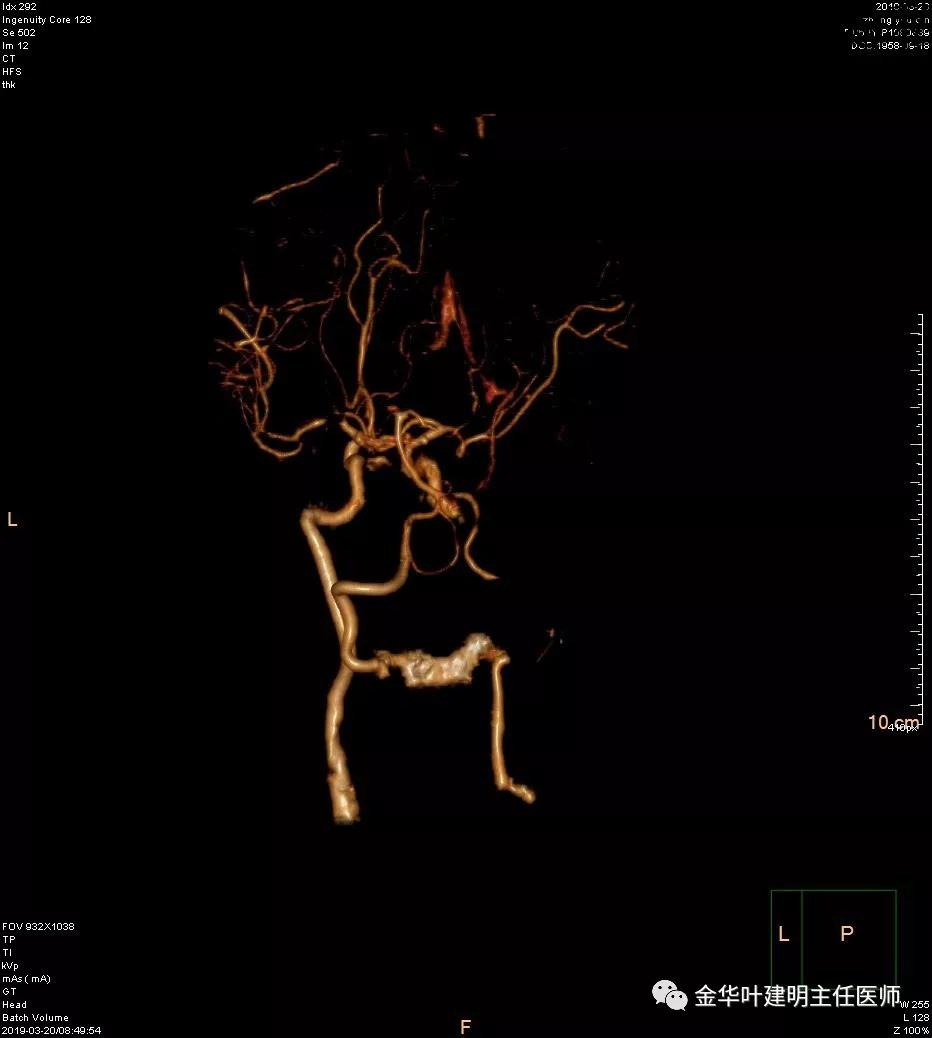

报告提示左侧大脑中动脉M1段及左侧大脑后动脉P1段管腔闭塞。按影像科的建议并请神经内科会诊后,予以行CTA检查。结果如下:

可见其左侧大脑中动脉起始部管腔重度狭窄,右侧大脑中动脉近段管腔也有狭窄;左侧大脑后动脉中远段未见显影。又建议其DSA检查。我们仔细询问章某平时没有神经系统的症状,回忆起来说大概3年前有段时间头昏比较明显,但也没有到大的医院详细检查,后来自行改善。鉴于平时并无明显症状,我们认为其脑血管的病变是慢性闭塞,并已经有侧支代偿。便先请神经外科会诊,会诊后的意见是可以先处理肺部疾病,待情况稳定后再到神经外科进一步诊治。这样,我们便打算为其进行手术。当然因为上叶病灶考虑良性,且位置靠肺外周部位,而下叶病灶考虑恶性,又是中肺叶中央,无法亚肺叶切除,况且病灶大于3厘米,密度虽还是混合磨玻璃,但已经明显偏向实性。所以拟定手术方式是“胸腔镜下左肺下叶切除+上叶楔形切除及纵隔淋巴结清扫术”,当然万一上叶也是恶性,也只能同样是这样的手术方式,全肺切除显然风险过高。